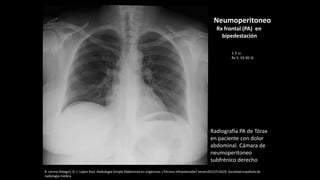

Radiografía PA de Tórax

en paciente con dolor

abdominal. Cámara de

neumoperitoneo

subfrénico derecho

Rx frontal (PA) en

bipedestación

1-2 cc

Rx S: 55-85 %